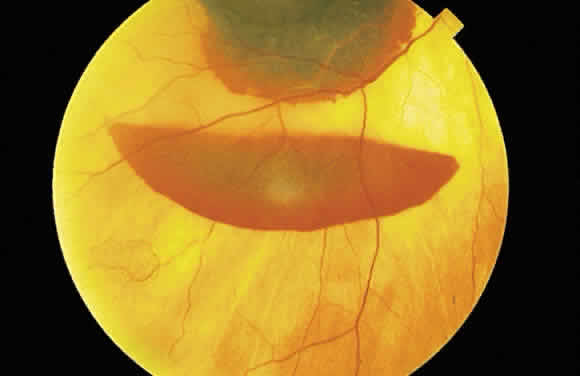

the internal limiting membrane (see Fig. 11B). A hemorrhage located between the retinal pigment epithelium and Bruch's

membrane also spreads in a plane parallel to the orientation

of the membrane (Fig. 12). However, its extent is limited by the adhesion of the pigment epithelium

to Bruch's membrane, in contrast to a nerve fiber layer hemorrhage, where

no such delineating structure is present. Therefore, a fresh

nerve fiber layer hemorrhage appears bright red and has feathery

borders, whereas a subpigment epithelial hemorrhage appears brown-black

and has sharp borders (Fig. 13).  Fig. 11. A. Section of retina with hemorrhage in the nerve fiber layer (between the two large arrows). Notice that the limits of the hemorrhage are not clearly defined, since

Fig. 12. Section of the eye showing subretinal hemorrhage. (Courtesy of Ralph C. Eagle Jr, MD, Philadelphia, PA) Fig. 12. Section of the eye showing subretinal hemorrhage. (Courtesy of Ralph C. Eagle Jr, MD, Philadelphia, PA)

Fig. 13. A. Fundus photograph of a subpigment epithelium hemorrhage superotemporal

to the disc secondary to a macroaneurysm. Notice its dark color and sharp

border. The central portion of the hemorrhage has extended through

the sensory retinal to the subinternal limiting membrane area. B. Fluorescein angiography showing the retinal vessels overlying the deep

hemorrhage but obscured by the central extension anteriorly. (B, courtesy of William Tasman, MD, Philadelphia, PA) Fig. 13. A. Fundus photograph of a subpigment epithelium hemorrhage superotemporal

to the disc secondary to a macroaneurysm. Notice its dark color and sharp

border. The central portion of the hemorrhage has extended through

the sensory retinal to the subinternal limiting membrane area. B. Fluorescein angiography showing the retinal vessels overlying the deep

hemorrhage but obscured by the central extension anteriorly. (B, courtesy of William Tasman, MD, Philadelphia, PA)